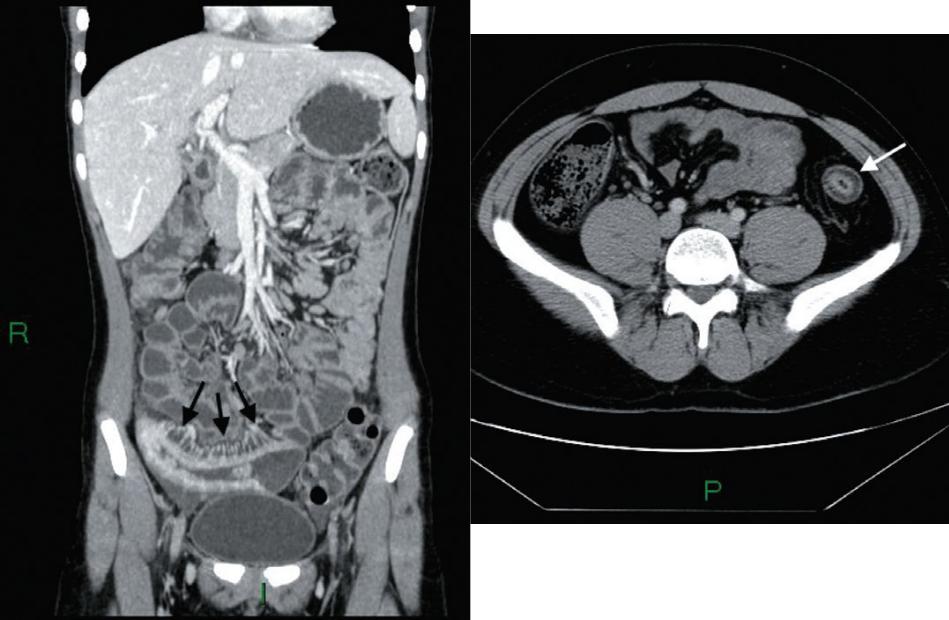

Болезнь Крона: рентгенологические признаки